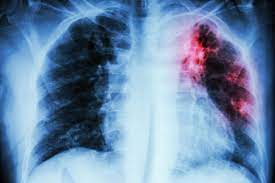

Asociación entre el uso de inhibidores de la bomba de protones y el riesgo de neumonía en niños

En este estudio de serie de casos autocontrolado a nivel nacional en Suecia, se observó un aumento del riesgo de neumonía tanto inmediatamente antes como inmediatamente después del inicio de los inhibidores de la bomba de protones (IBP). Es probable que este patrón de asociación se explique por un riesgo subyacente de neumonía debido a factores presentes de forma transitoria en el momento del inicio del IBP. Por lo tanto, nuestros hallazgos no respaldan una relación causal entre el uso de IBP y el riesgo de neumonía.